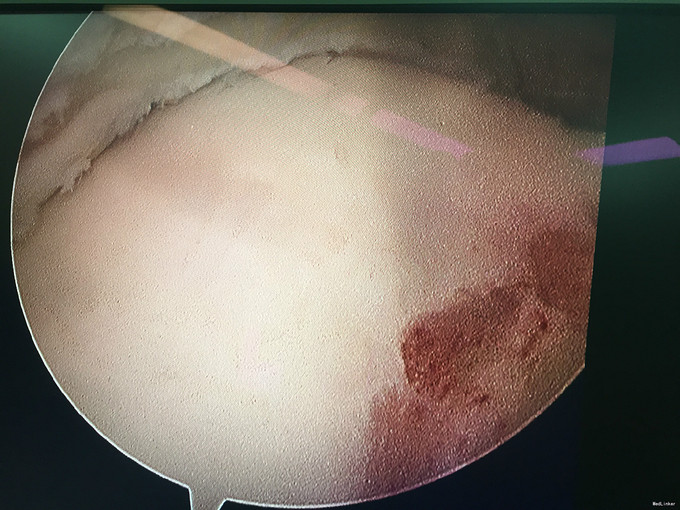

入院诊断:右踝前方撞击综合征、右距骨骨软骨瘤、右踝滑膜炎 治疗:入院完善术前检查后行右踝关节镜下滑膜清理+前方撞击成形+距骨骨软骨瘤切除。

随访:患者术后6周,踝关节活动度恢复正常,正常行走。 讨论:本病例系关节镜结合切开手术的范例,术中见踝关节内滑膜非常像色素沉着绒毛结节性滑膜炎,但未得到病理证实。还需要长期的随访来判断。